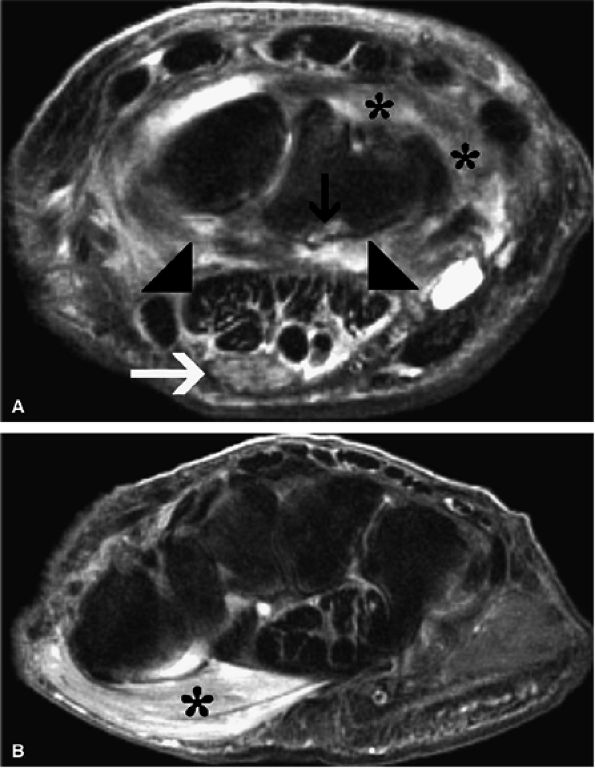

FIGURE 12.41 ● Carpal tunnel syndrome and rheumatoid arthritis. (A) Axial fat-suppressed T2-weighted image at the level of the proximal carpal row shows swelling and edema of the median nerve (white arrow) associated with flexor tendinosis (arrowheads), erosive changes (black arrow), and extensive inflammatory pannus (asterisks). (B) Axial fat-suppressed T2-weighted image at the level of the hook of the hamate demonstrates denervation edema of the thenar muscles (asterisk).

|

FIGURE 12.42 ● Carpal tunnel syndrome and flexor tenosynovitis. Axial fat-suppressed T2-weighted image demonstrates marked peritendinous inflammatory edema of the flexor tendons within the carpal tunnel consistent with tenosynovitis (open arrows). Note flattening and edema of the median nerve (arrow) and associated synovitis in this patient with rheumatoid arthritis (asterisk).